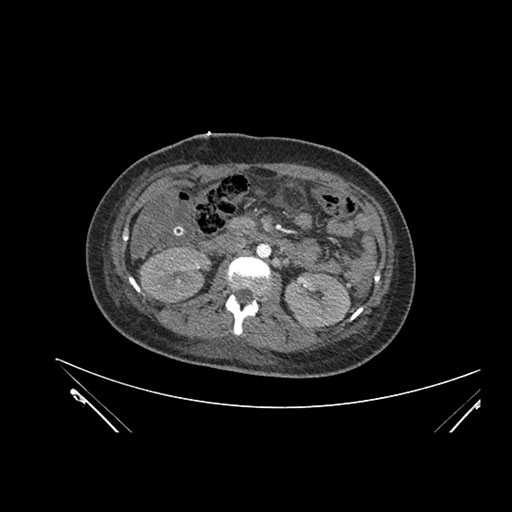

Axial Arterial

Axial Venous

Imaging analysis

Based on initial findings, which issue(s) would you be most concerned about?